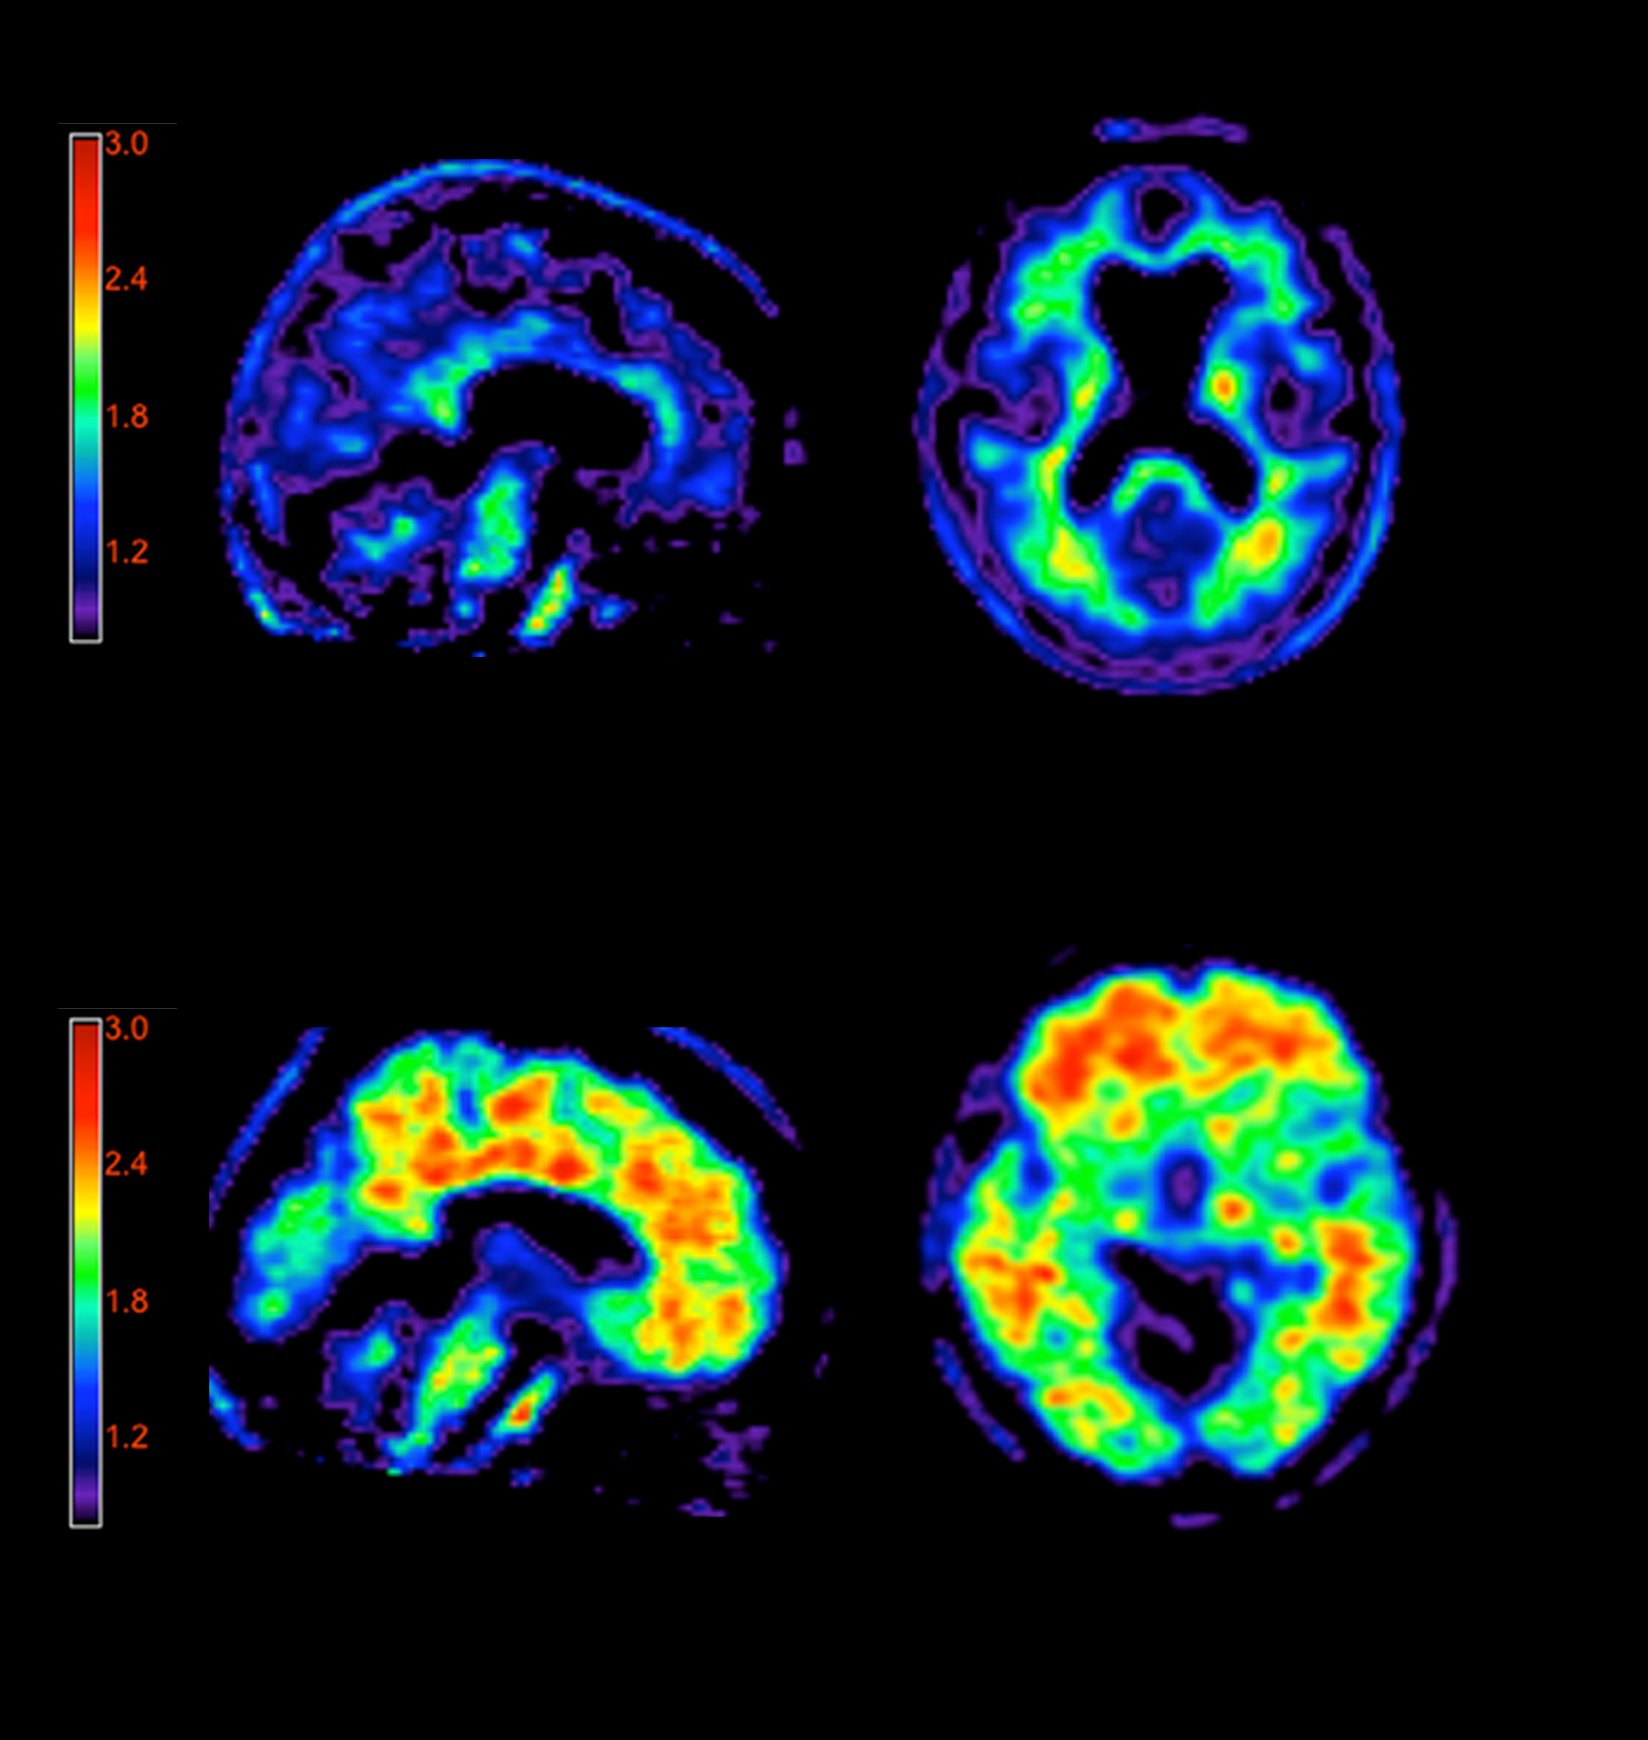

Statistical Parametric Maps Of Flortaucipir Positron Emission Download Scientific Diagram

Figure 4 From Cerebral 18 F T807 Av1451 Retention Pattern In Clinically Probable Cte Resembles Pathognomonic Distribution Of Cte Tauopathy Semantic Scholar

Figure 1 From Pet Scanning Of Brain Tau In Retired National Football League Players Preliminary Findings Semantic Scholar